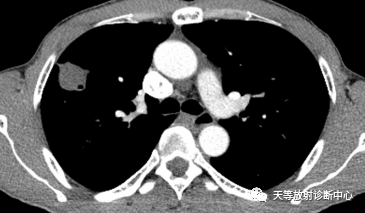

▲阻塞空洞型,由阻塞空洞充满干酪性物质形成,近端见支气管狭窄;

②厚包膜强化型:病变显示包膜有较厚的新鲜肉芽组织,与病灶中心的干酪坏死灶交界不规则;

③菲薄的包膜强化型:病灶包膜的肉芽组织较薄,与病中心的干坏死灶交界线清楚。